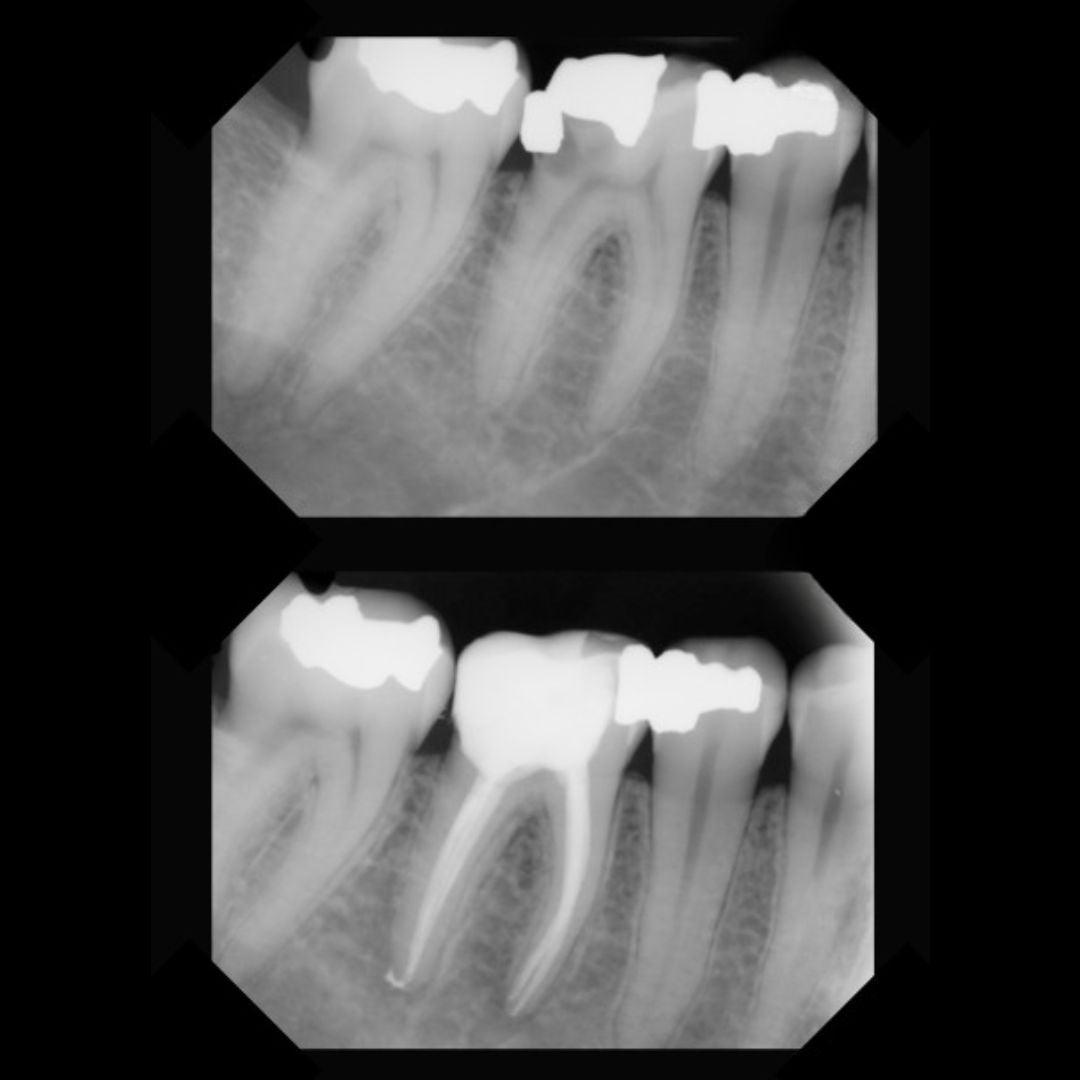

Hos oss blir rotfylling alltid utført av erfarne tannleger med spesialkompetanse innen endodontisk behandling. Vi benytter digital røntgen og mikroskop for å sikre høy presisjon og optimal rensing av rotkanalene. Bedøvelse gis alltid for at du skal kjenne minst mulig under prosedyren, og vi tilpasser behandlingen etter dine behov og tannens tilstand.